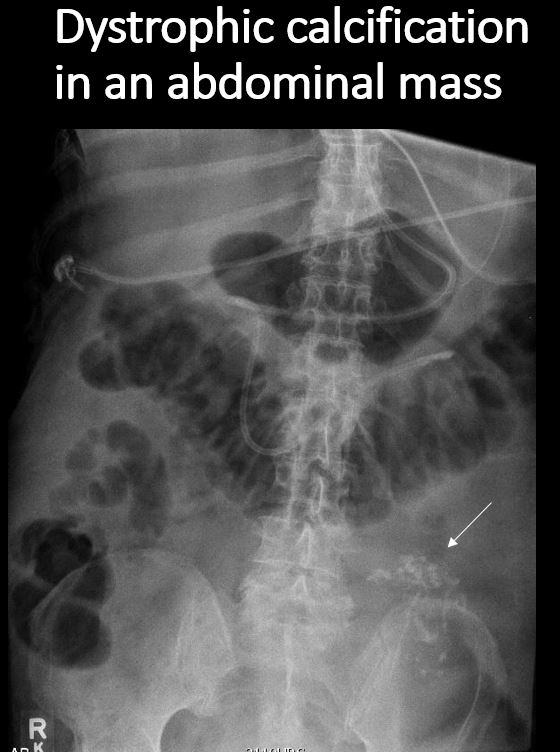

There are dystrophic or additional intra-abdominal soft tissue calcifications. [Yes/No]